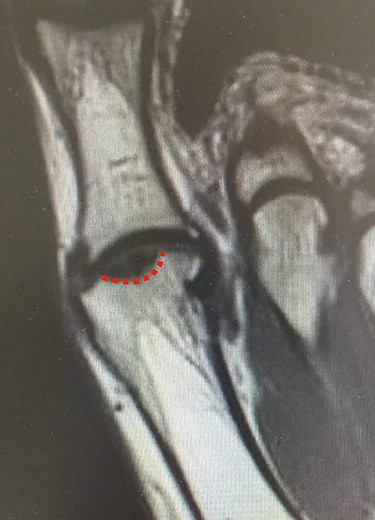

MRI of the left foot, shows low signal intensity lesion on the MH. The red dots show the depth of a subchondral cyst formation.

Standing anteroposterior (AP), oblique and lateral radiographs of the affected foot were taken. On the AP and oblique views, an OD lesion of the 1st MH was visible (lytic lesion of the subchondral bone and subchondral sclerosis formation) with a lateral-forming osteophyte (Fig. 1A and B). Magnetic resonance imaging (MRI) of the left foot clearly shows the osteochondral defect of the 1st MH (Figs 2 and 3).